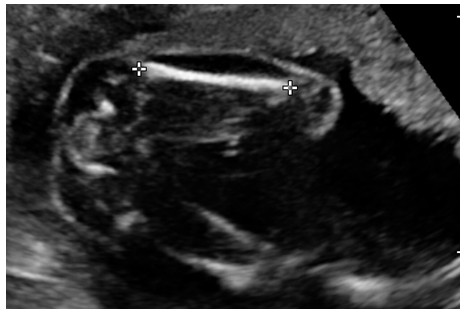

(二)胎儿颈项部位透明层(Nuchal translucidity ,NT)厚度测量,见图3

图3 胎儿颈项部位透明层

检查孕周在11-13周+6天之间进行,测量方法:在胎儿体位自然屈曲时,取正中矢状切面时,显示胎儿颈背部皮下组织,测量其皮肤与脊柱表面软组织间无回声区的最大径线。 NT正常值≤0.30cm, NT大于正常,据文献报道约10%为胎儿染色体异常,应建议临床医师行染色体检查。 NT正常范围:孕10周≤0.18cm, 孕11周≤0.19cm,孕12周≤0.21cm,孕13周≤0.25cm,也可采用平均值孕10-13周,NT≤0.25cm。见图4